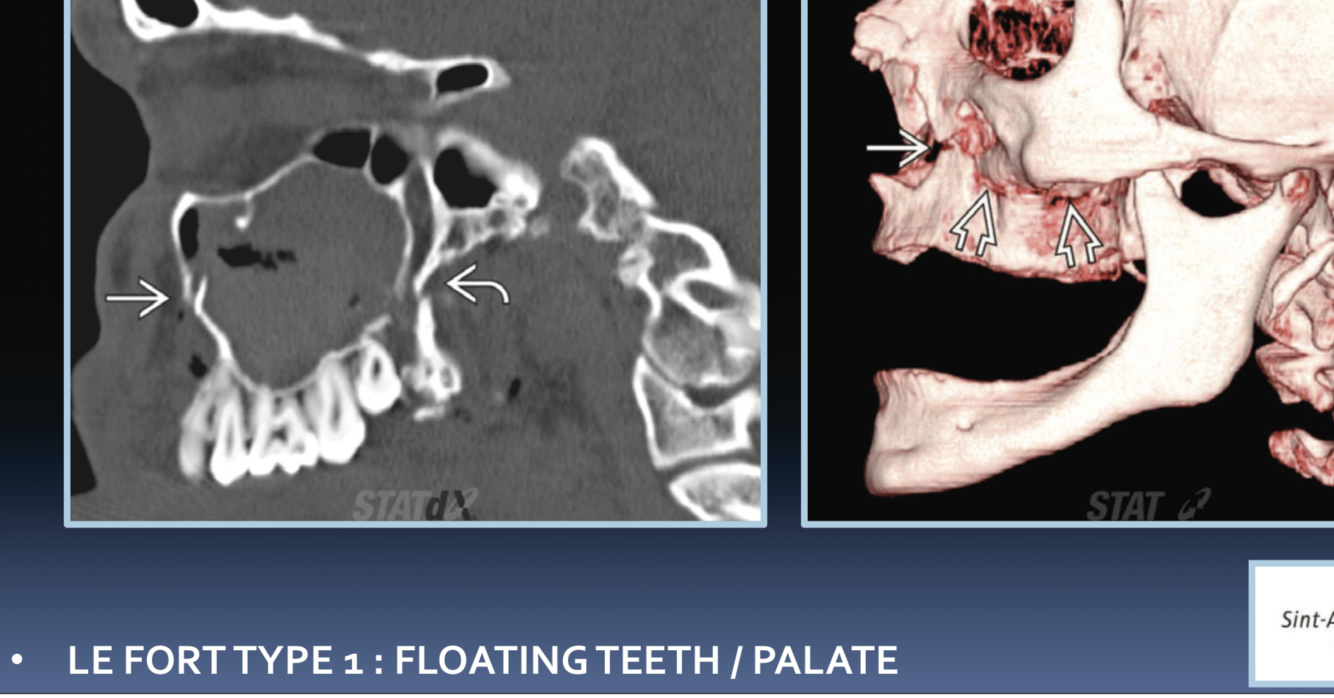

LeFort types?